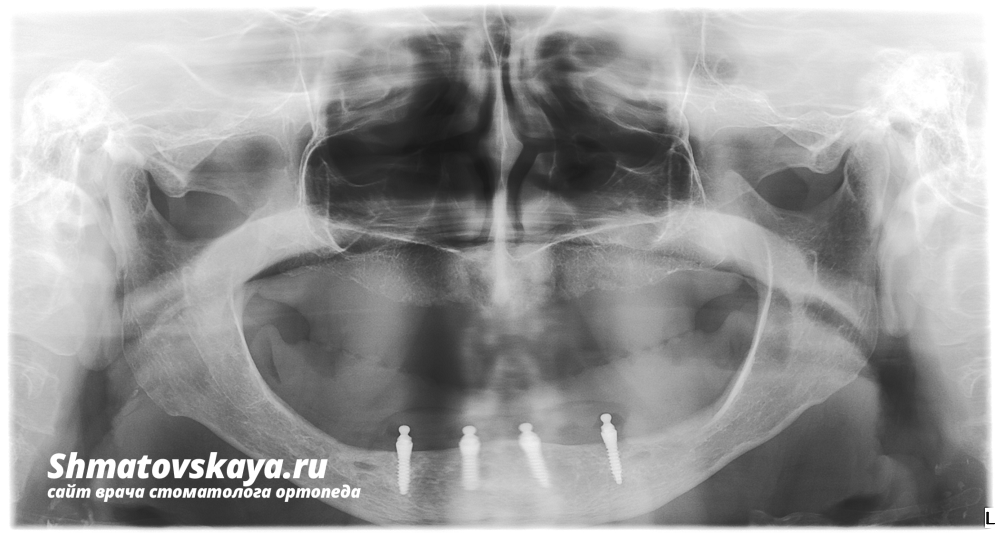

Объективно: на верхней челюсти наблюдается средняя степень атрофии альвеолярного отростка,альвеолярные бугры  сохранены, нёбный свод выражен; на нижней челюсти альвеолярный отросток отсутствует, слизистая оболочка протезного ложа тонкая, атрофичная.

1. На нижнюю челюсть установлено 4 мини-имплантата